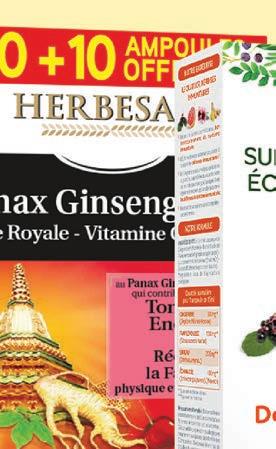

HERBESAN

20